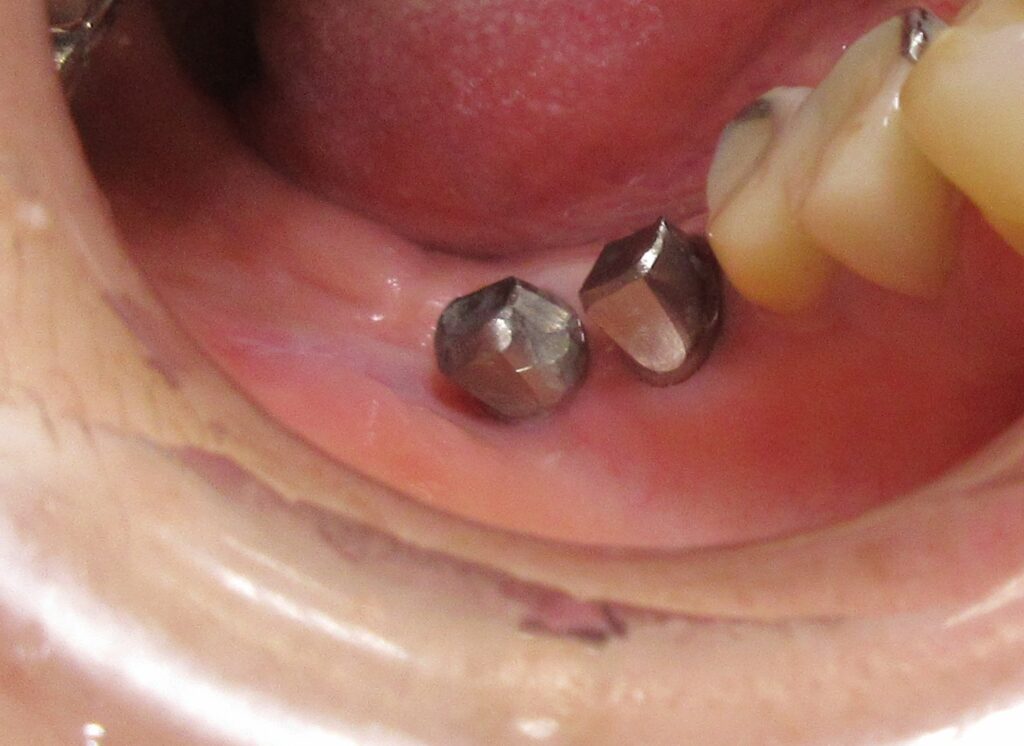

開けた穴に、専用道具を使ってネジを締めるように長さ2センチ程のインプラントを骨に埋め込んでいきます。

続けて他の歯も同じように植立していきます。

インプラントオペでは、複数本を植立する場合でも、当時進行はせず、1本ずつ同じ工程を繰り返して植立します。

しっかりとインプラント埋め込まれた後は、動揺がないか、噛んだ時に当たらないかなどを確認して、最後にパノラマ写真を撮影して今回のオペは終了となりました。